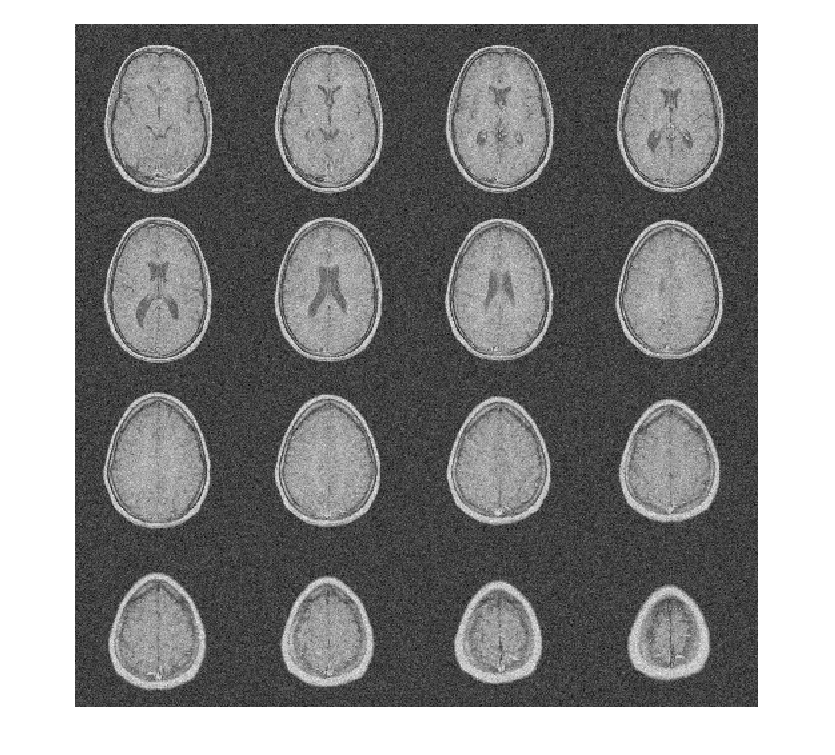

Чтобы продемонстрировать это, рассмотрите набор данных MRI, состоящий из 16 срезов. Гауссов шум со стандартным отклонением 10 был добавлен к исходному набору данных. Отобразите шумный набор данных.

load MRI3D montage(reshape(noisyMRI,[128 128 1 16]),'DisplayRange',[])

Обратите внимание на то, что исходный ОСШ до шумоподавления составляет приблизительно 11 дБ.

20*log10(norm(origMRI(:),2)/norm(origMRI(:)-noisyMRI(:),2))

ans = 11.2997

Denoise набор данных MRI вниз к уровню 4 с помощью и DTCWT и DWT. Подобные длины фильтра вейвлета используются в обоих случаях. Постройте получившийся ОСШ как функцию порога. Отобразите denoised результаты и для DTCWT и для DWT, полученного в лучшем ОСШ.